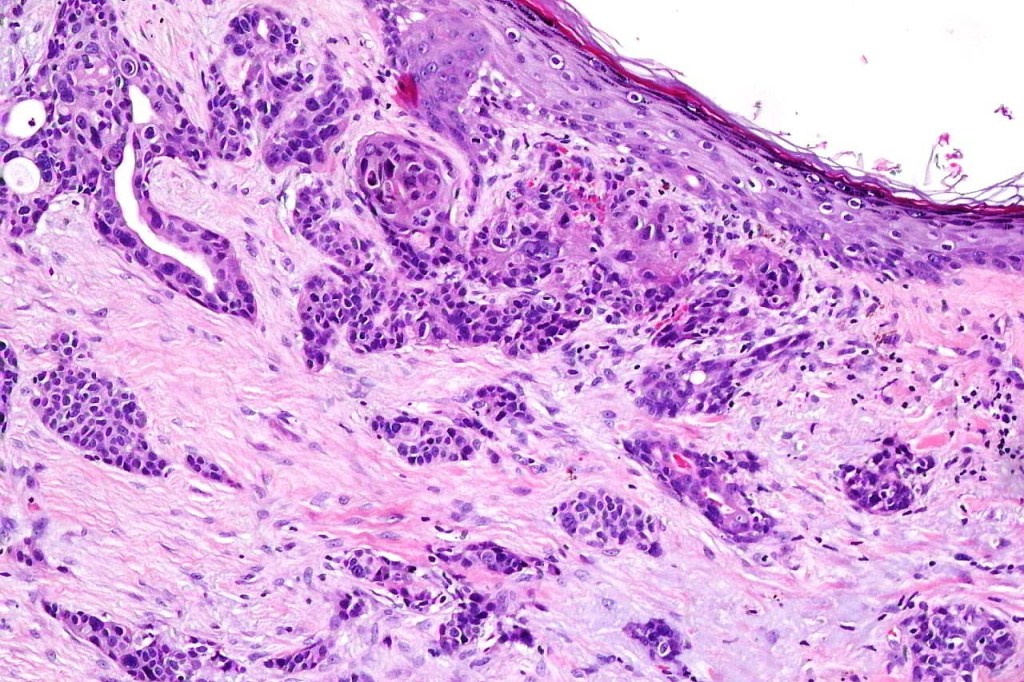

•Ulceration and solar elastosis are common

•Superficial SCC

•Variable pleomorphism and mitotic activity

•Often extends to the subcutaneous fat